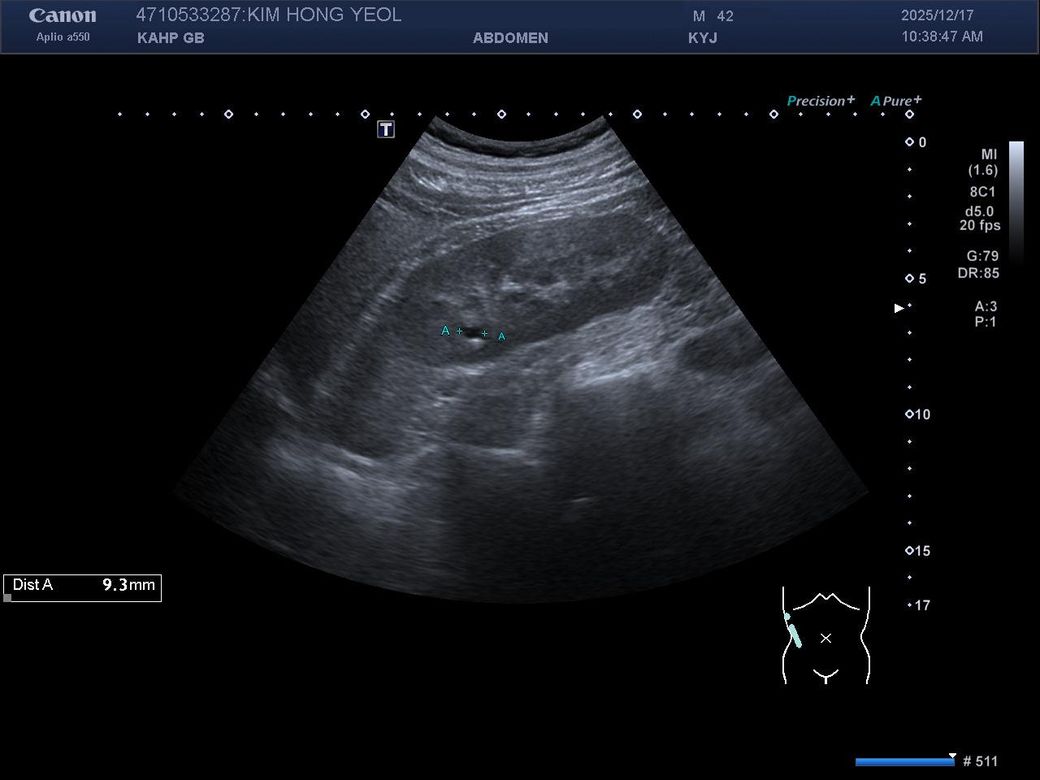

• 비뇨기과를 가시는 것이 맞고, 제공해주신 MRI와 초음파 소견을 종합하면, 양측 신장에 병변이 보이기는 하나 형태가 서로 다릅니다. 한쪽은 비교적 경계가 명확하고 밝게 보이는 병변으로 낭종 가능성이 우선 고려되고, 반대쪽은 내부 신호가 혼재된 형태로 단순 낭종 외의 병변 가능성도 완전히 배제하기는 어렵습니다. 다만 단일 컷 이미지로는 조영 증강 여부, 내부 구조, 혈류 평가가 제한되어 확정 판단은 불가능합니다.

임상적으로 중요한 기준은 단순 낭종인지, 복합 낭종인지, 혹은 고형 종양인지 구분하는 것입니다. 단순 낭종이면 추가 치료 없이 경과관찰이 원칙이고, 복합 낭종이나 고형 병변이면 추가 평가가 필요합니다. 이 구분은 조영증강 CT 또는 조영 MRI에서 보스니악 분류 기준으로 판단합니다.